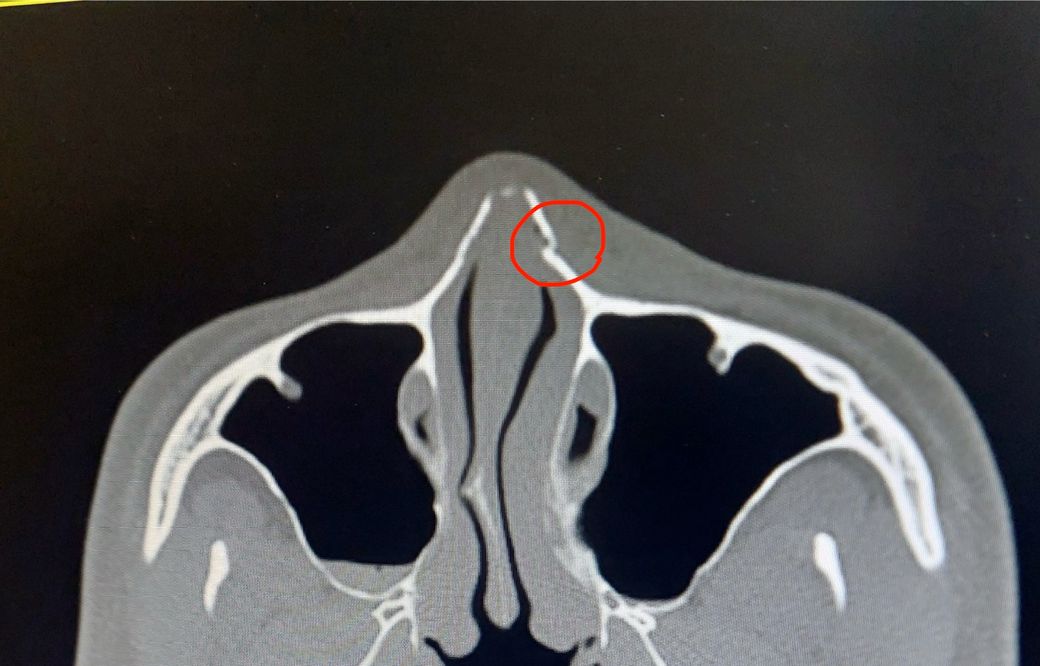

제공하신 CT 이미지 기준으로만 말씀드리면, 붉은 표시 부위는 코뼈(비골) 상부에 비교적 얇은 골절선 또는 약간의 함몰로 보입니다. 다만 CT 1컷만으로 정확한 변위(밀린 정도)와 측면 변형 여부를 완전히 판단하기는 제한이 있습니다. 그 점을 전제로 설명드립니다.

1. 수술 필요 여부

변위(뼈가 밀린 정도)가 크지 않고, 외형 변형이 거의 없다면 보존적 치료(수술 없이 경과관찰)로 가는 경우가 많습니다. 실제 비골골절은 경미한 변위면 굳이 수술하지 않아도 기능·외형 모두 큰 문제 없이 회복되는 경우가 많습니다.

2. 수술하지 않아도 붙을 수 있는지

붙습니다. 코뼈는 얇지만 혈류 공급이 좋아 대부분 4~6주 사이에 자연 유합이 됩니다. 문제는 “잘” 붙느냐, 즉 모양이 틀어지지 않느냐입니다. 변위가 크면 모양이 틀어진 채 붙을 수 있습니다.

3. 6주 후 강도

정상적으로 붙으면 6주 이후엔 쉽게 “톡 치면 부러지는” 수준이 아닙니다. 일상 충격에는 충분히 견딜 정도로 안정됩니다. 다만, 초기 2~3주는 외부 충격에 취약하므로 조심이 필요합니다.

결론

현재 이미지 한 컷 기준으로는 크게 밀린 골절은 아닌 것으로 보여, 대부분은 수술 없이 회복 가능한 범주에 들어갑니다. 다만 변위 평가가 핵심이라, CT 전체를 본 성형외과·이비인후과 전문의의 판단이 최종적으로 필요합니다.